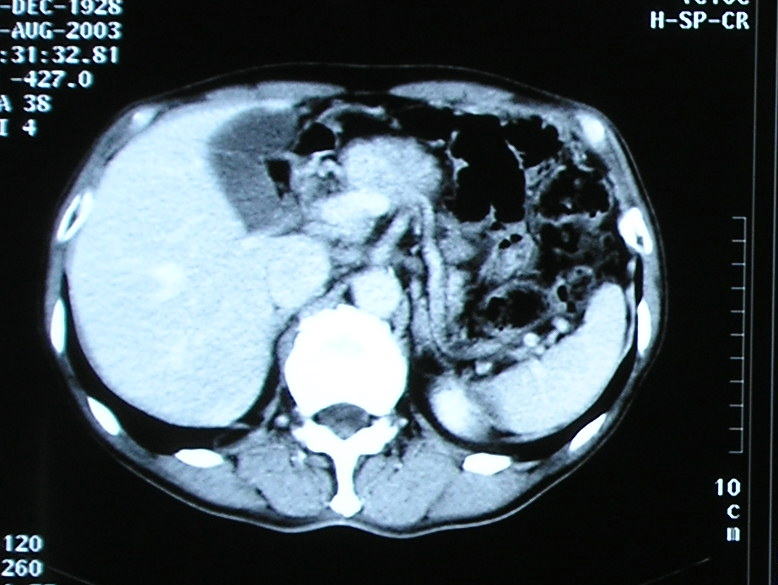

慢性膵炎

体重減少、DMの悪化が出現。

MRCP,膵液細胞診、超音波内視鏡を経て

診断された。経過 良好。

腹部CTで 拡張した主膵管をみとめる。